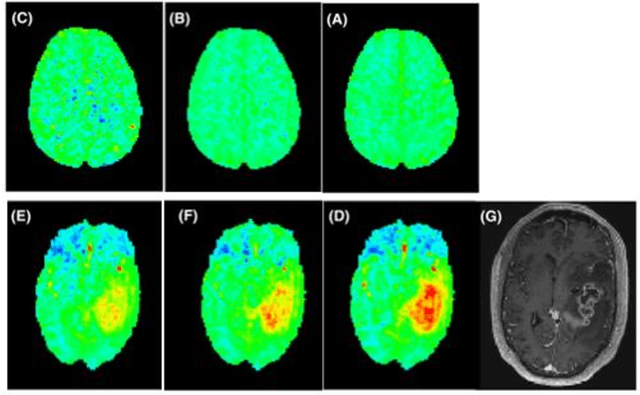

Abstract:Magnetic resonance imaging (MRI) relies on radiofrequency (RF) excitation of proton spin. Clinical diagnosis requires a comprehensive collation of biophysical data via multiple MRI contrasts, acquired using a series of RF sequences that lead to lengthy examinations. Here, we developed a vision transformer-based framework that captures the spatiotemporal magnetic signal evolution and decodes the brain tissue response to RF excitation, constituting an MRI on a chip. Following a per-subject rapid calibration scan (28.2 s), a wide variety of image contrasts including fully quantitative molecular, water relaxation, and magnetic field maps can be generated automatically. The method was validated across healthy subjects and a cancer patient in two different imaging sites, and proved to be 94% faster than alternative protocols. The deep MRI on a chip (DeepMonC) framework may reveal the molecular composition of the human brain tissue in a wide range of pathologies, while offering clinically attractive scan times.